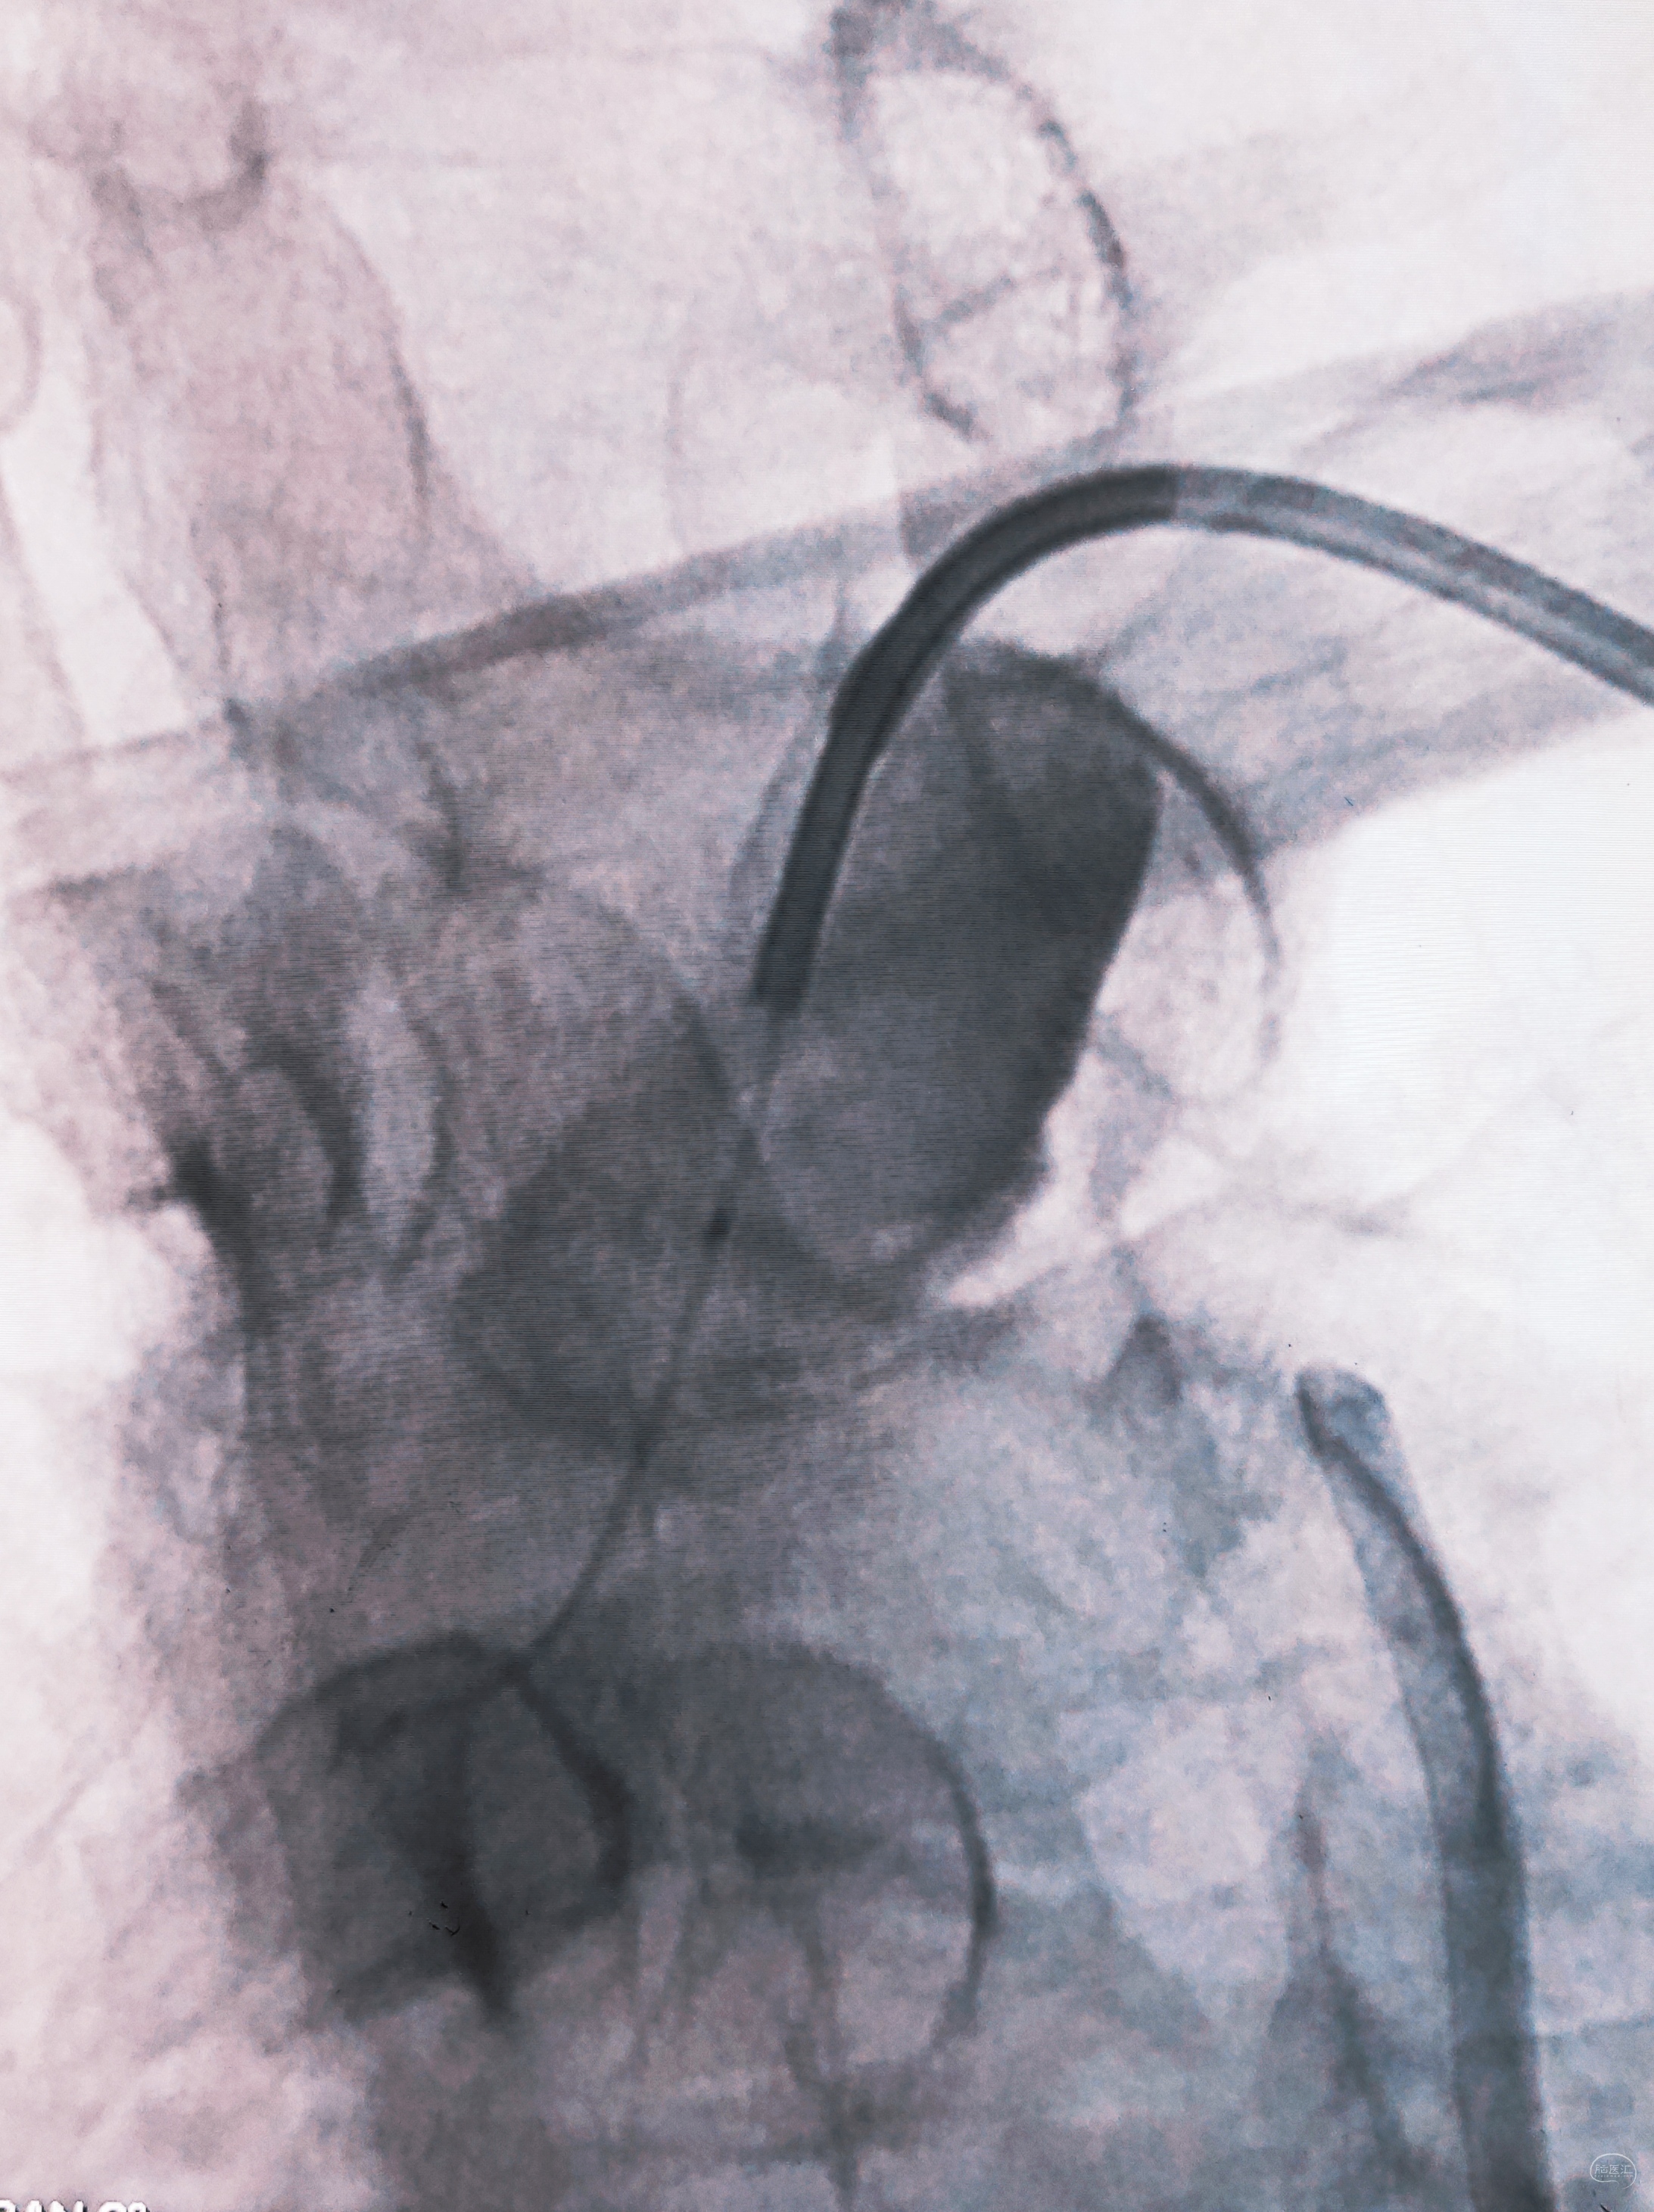

弓上造影初见:问题(一)左侧锁骨下动脉闭塞,主诉为头晕,双上肢收缩压差>20mmHg,这就是祸根?接着看弓上造影晚期像。

弓上造影晚期:剂量因素,逆流盗血隐隐可见,复合预期,那就看看对侧椎动脉情况吧